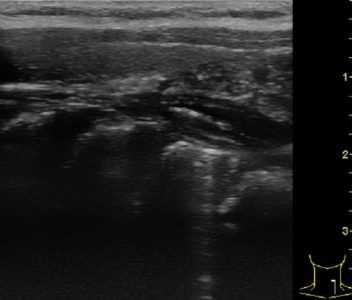

| Фото. А — Поперечный срез тимуса у новорожденного. Б — У детей раннего возраста, особенно при крике, верхняя часть тимуса может подниматься на шею через яремную вырезку, тогда он определяется позади щитовидной железы (звездочка). В — На саггитальном срезе хорошо видно, что тимус (эктопическая долька на шее) гипоэхогенный по сравнению с щитовидной железой. | ||